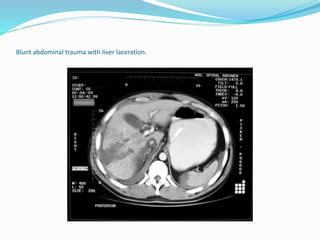

Blunt abdominal trauma with liver laceration.

Blunt abdominal traumawith liver laceration.